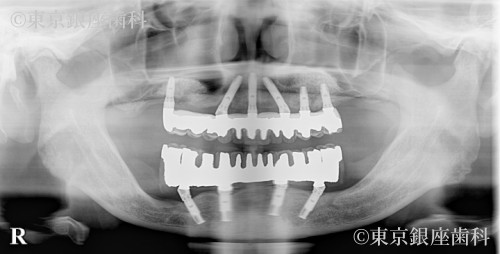

難しい神経位置の症例で回復まで半年以上を要した60歳代男性のインプラント症例

下顎の神経露出に近い難症例。術後一時的に神経麻痺が出たが、理学療法と投薬で半年以上かけて回復。信頼関係の中で上顎治療も希望され、現在は上下とも安定。

上下ワンデイインプラント(サイナスリフト併用)

腫れ・痛み・出血、神経麻痺、治癒遅延の可能性

術後のしびれ・麻痺感・違和感